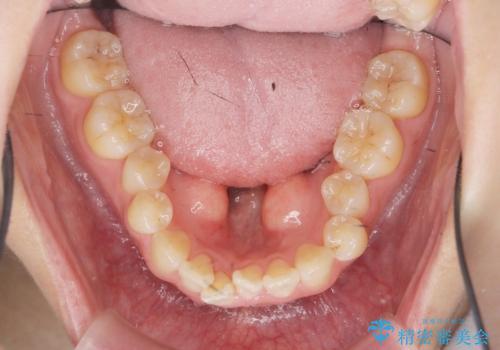

- マウスピース矯正を行うにあたり、舌のスペースが狭くなってしまうことから骨隆起の除去を希望されました。

舌のスペースが広くなったと喜んでいただくことができました。

反対側も除去を予定しています。